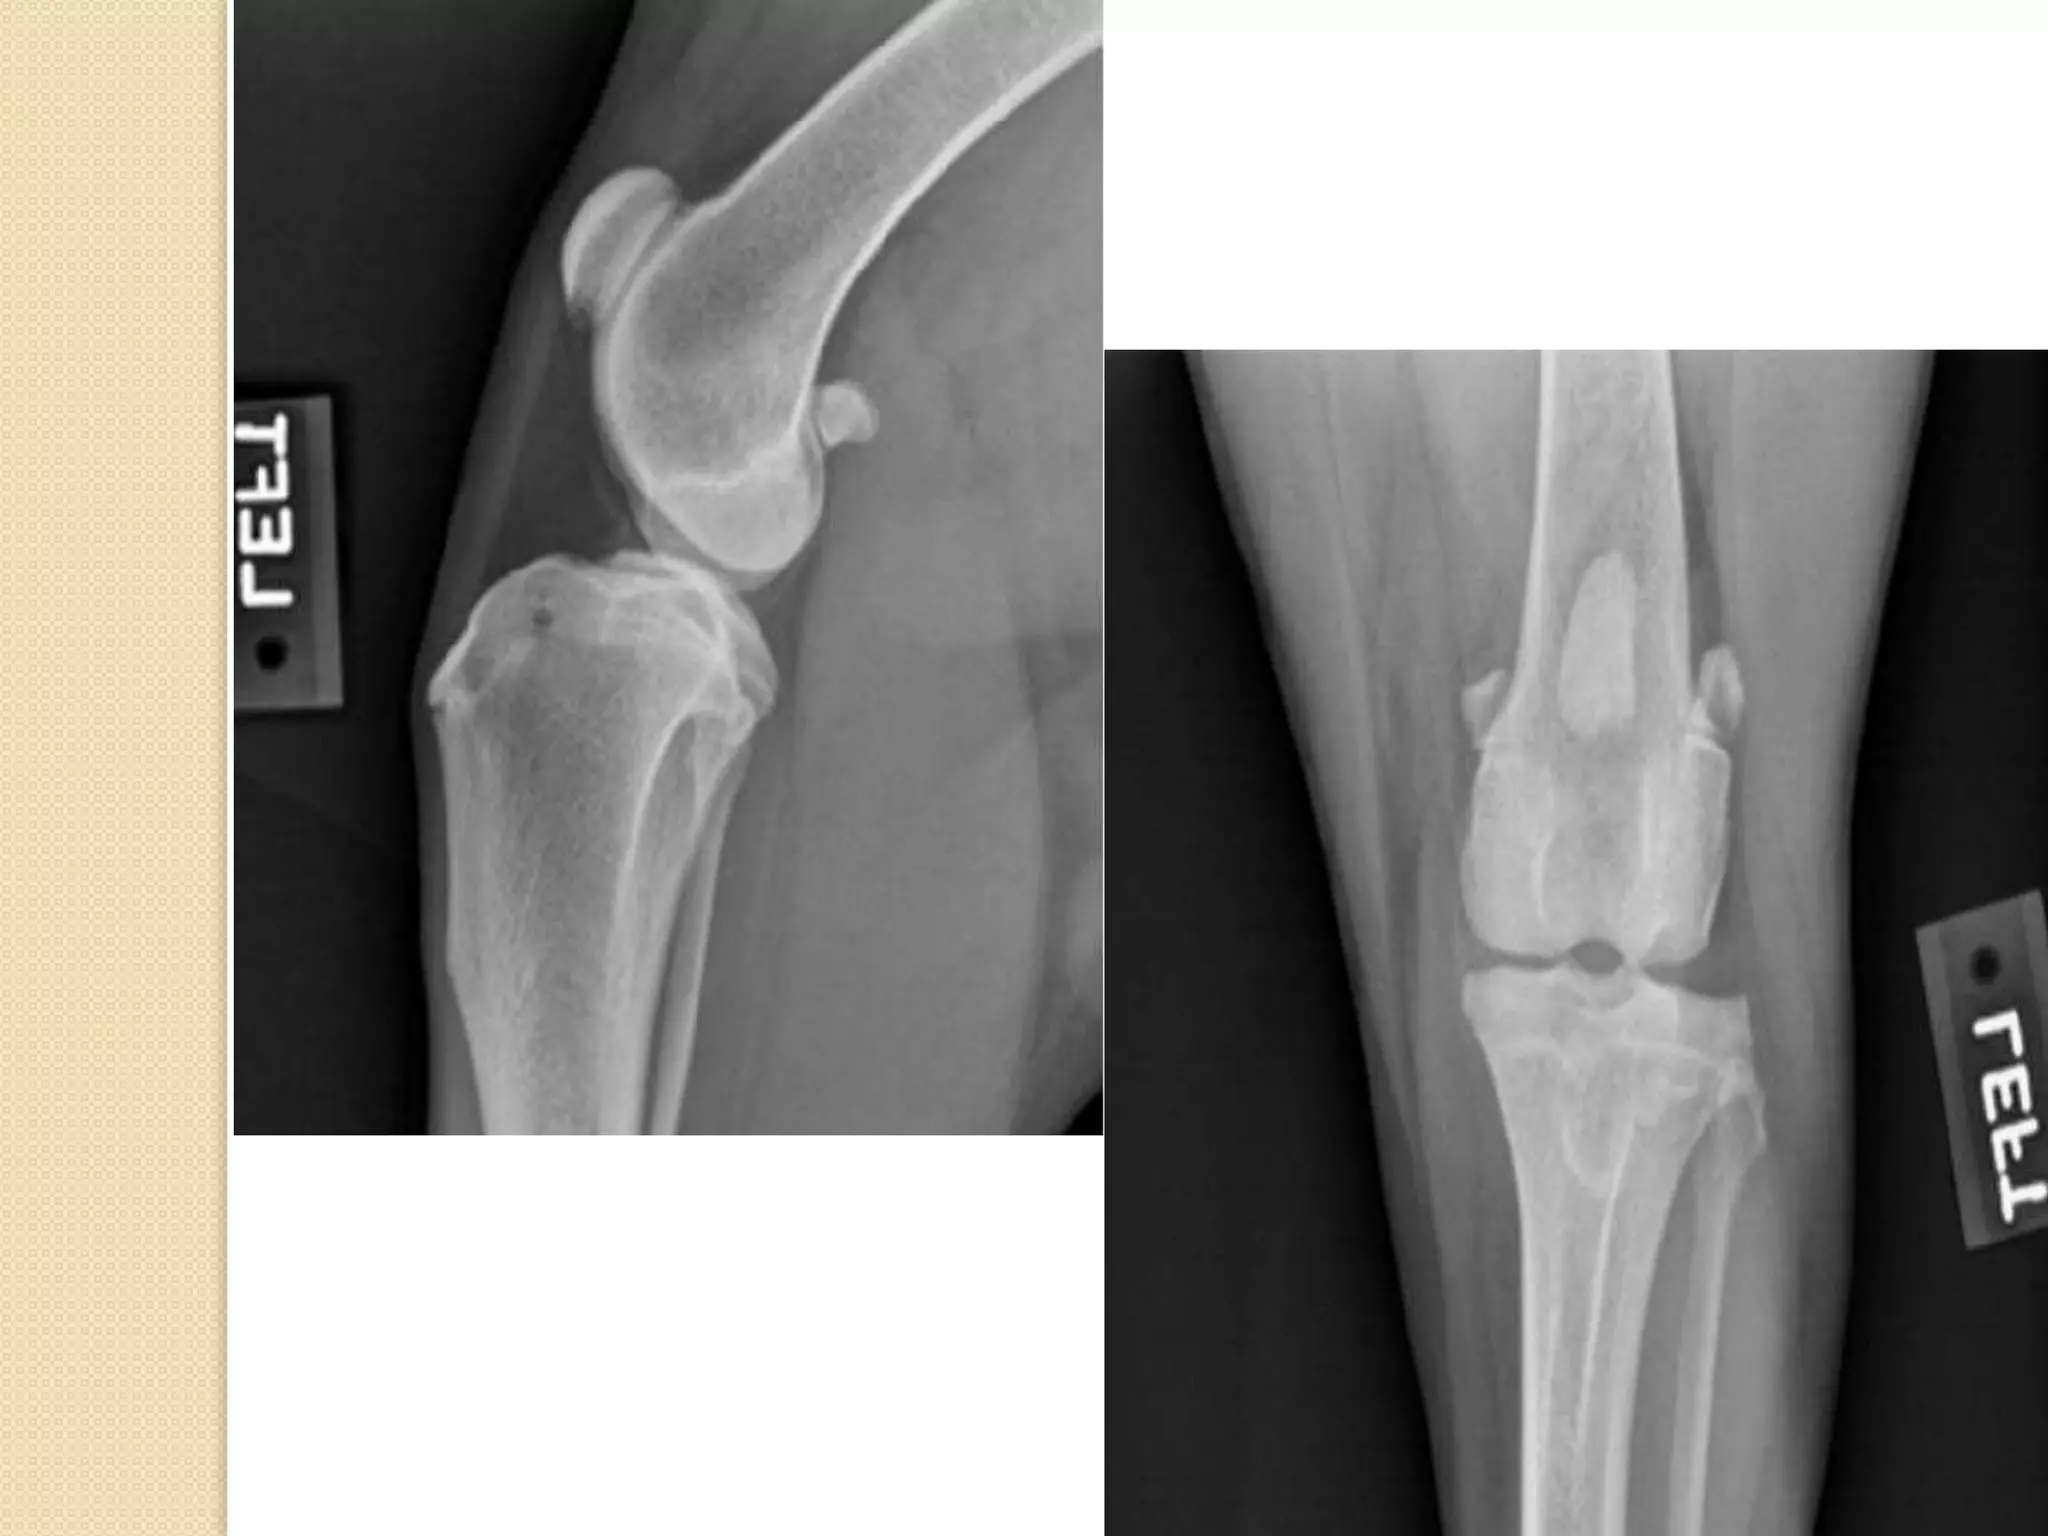

Stifle joint :

Stifle joint is a compound joint which is

formed of 3 bones (distal extremity of femur

– proximal extremity of tibia – patella)

Fibula , tibia and patella :

B= tibia

C= fibula

D = Patella

The fibula (B) is lateral to

the tibia (A), and the tibial

tuberocity (C) and tibial

crest (D) are on the cranial

aspect of the tibia. This

means that image one is a

cranial view and image two is

a lateral view of the left

tibia and fibula.

The tibial tuberosity is on

the proximal aspect of the

tibia